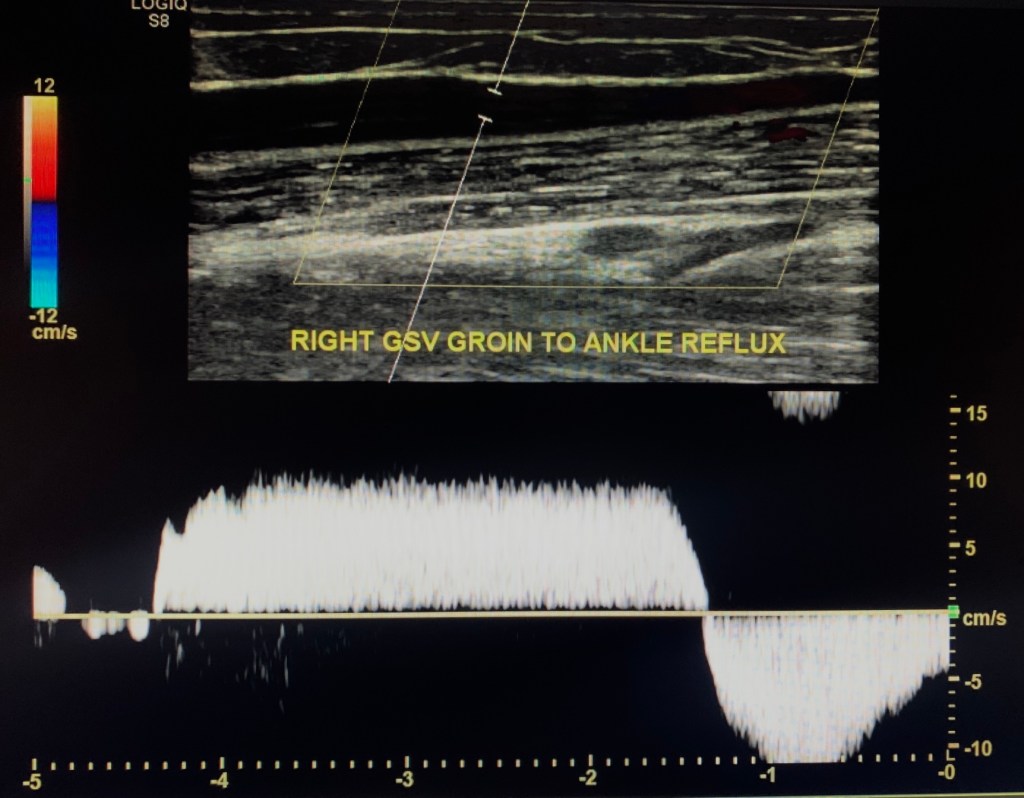

Great Saphenous Vein

Ask if there’s a history of GSV harvesting. The Great Saphenous Vein (GSV) is evaluated next for incompetence.

This patient demonstrated severe venous reflux in the GSV from the groin to ankle.

Measure the diameter of the incompetent GSV areas in transverse.

In this case we measure the entire length (proximal to distal thigh and proximal to distal calf).